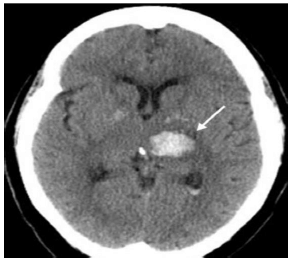

Paciente de 25 anos, do sexo feminino, usuária de anticoncepcional oral combinado, obesa, tabagista, sem outras comorbidades.

Internada na UTI com relato de cefaleia progressiva, em peso, com piora nas últimas 24h, agora bastante intensa e associada a náuseas e a vômitos.

Diante desse caso, foi realizada a tomografia de crânio que gerou a imagem a seguir.

Enunciado 3137179-1

A conduta adequada para essa doente é o(a)